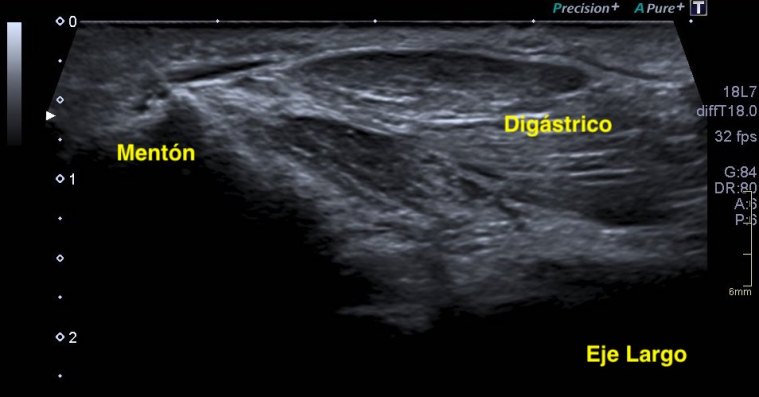

Los vientres anteriores de los músculos Digástricos, que son el objeto del desarrollo de este Post, son dos estructuras musculares redondeadas en el corte transversal, imagen 1, y alargados si los estudiamos en el eje largo, imagen 3, mira:

Ecográficamente los músculos digástricos en eje corto tienen semiología hipoecogénica, en aspecto de noche estrellada, como la de hoy, y en el eje largo en forma de penacho o en forma de plumas con las fibras alargadas y paralelas a la superficie.